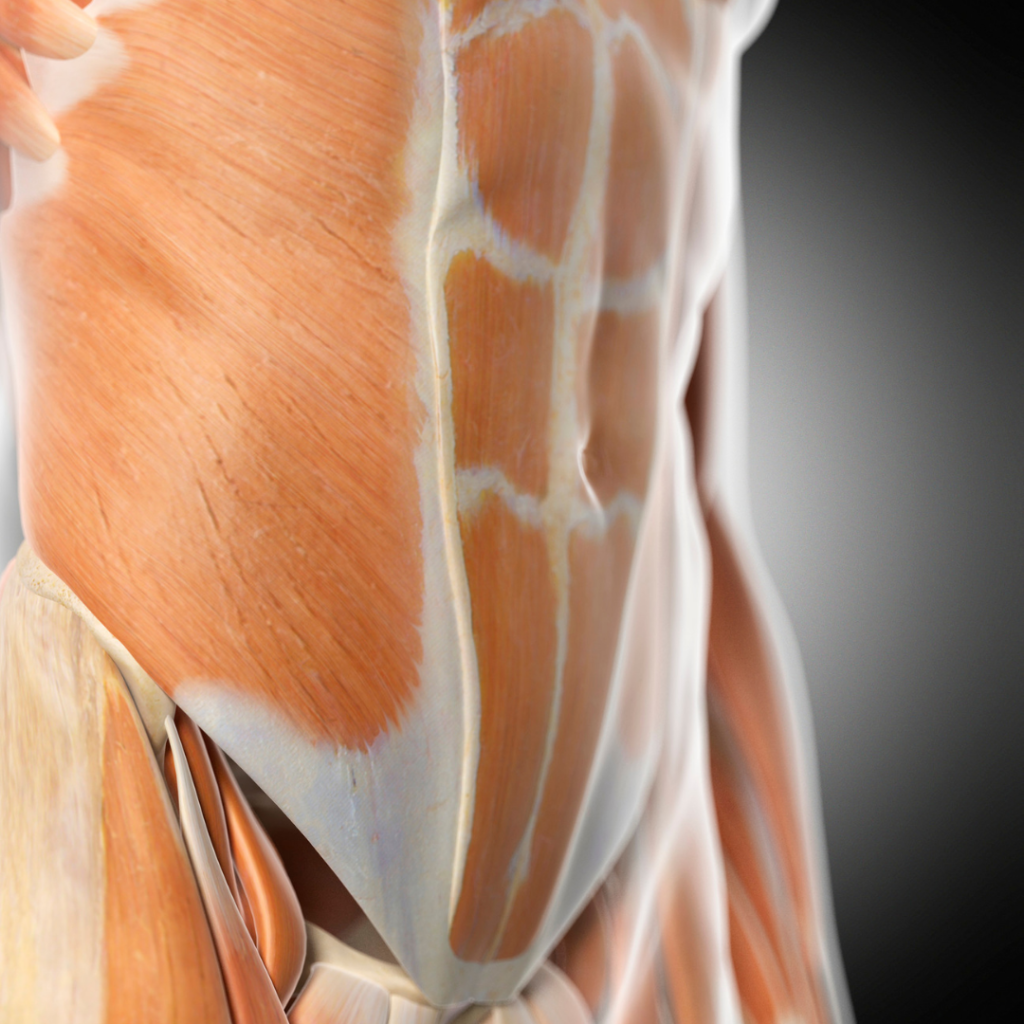

Szétnyílt hasizom a terhesség után

A szétnyílt hasizom, vagyis a „hatos” izmok részleges vagy teljes elválasztódása sajnos nagyon gyakori a terhesség alatt és után. Ennek oka, hogy a méh kinyújtja a hasi izmokat, ahogy növekedik a baba. A várandósság alatt minden nőnek szétnyílik a hasizma. Leggyakrabban a terhesség alatt és a szülés után tapasztalható.

A túlzott belső hasi nyomás szétnyílt hasizmot okoz. Terhesség alatt a hasizmok és a kötőszövetek megnyúlnak a táguló méh hatására. De szülés közben a nyomás hatására is kialakulhat.